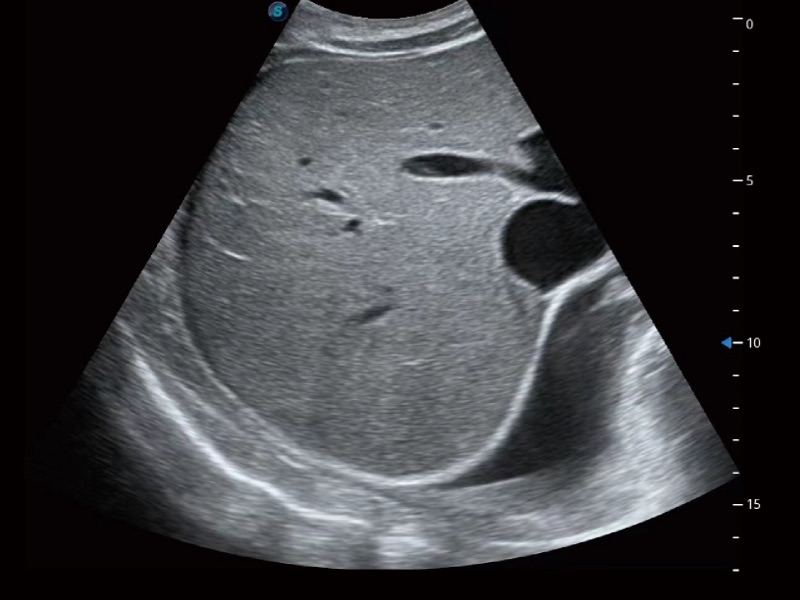

腹部应用

宽频带及多频段变频结合美狮贵宾会官网频率复合技术,使得每一支探头可以很好地给临床带来穿透力与分辨率的完美结合,图像真实,提供临床诊断准确性。

微米成像技术大大提高了器官和病变的可见性。高清对比度分辨率将抑制斑点噪声,同时保持真实的组织结构。